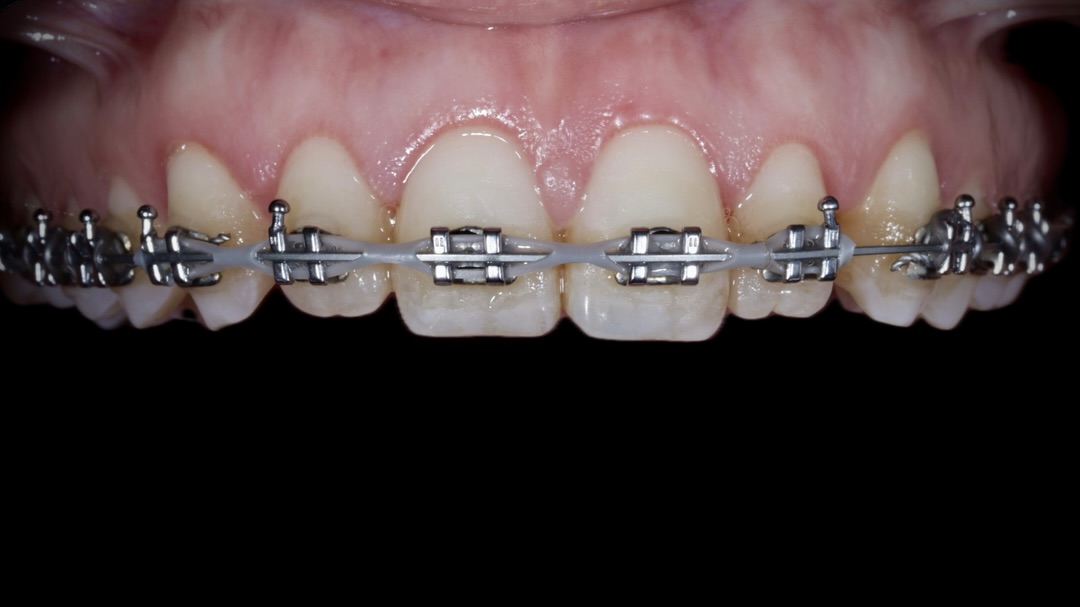

Formación Advance dirigida a doctores que quieran perfeccionar sus tratamientos de ortodoncia invisible y mejorar su planificación clínica.

Recomendada para doctores que ya trabajan con el sistema QuickSmile y para doctores que quieren profundizar en ortodoncia invisible, abordando

Si quieres dar un salto cualitativo en tu práctica clínica y trabajar con un sistema que realmente optimiza la mecánica ortodóncica, el Curso en Ortodoncia Autoligable con Sistema CCO® de la Universitat Internacional de Catalunya (UIC Barcelona) es una oportunidad para profundizar en un

La Ortodoncia ha sido objeto de una profunda evolución en sus formas de tratamiento, y con las técnicas de Alineadores Invisibles, se ha revolucionado las posibilidades de tratamiento. Esta técnica nos permite corregir la posición dental sin que nadie se dé cuenta; solo el paciente sabe que